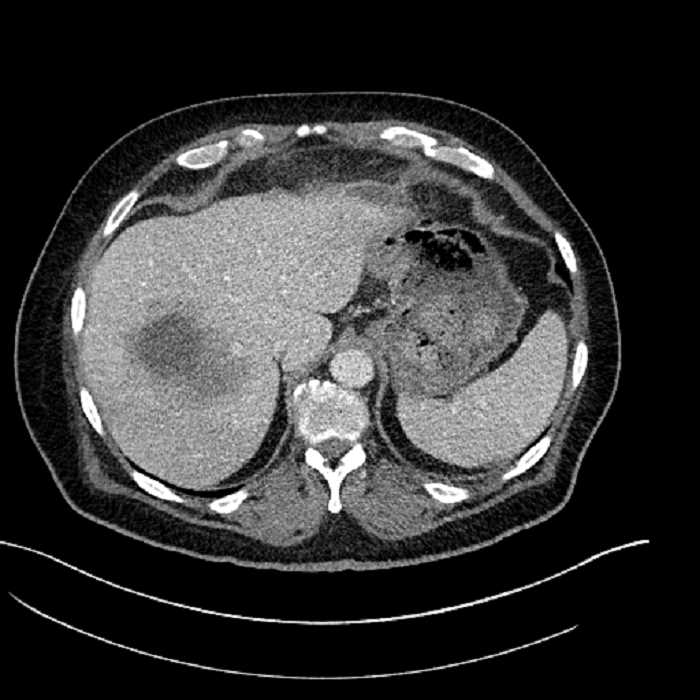

• Large fluid density structure in hepatic segments 7 and 8 measuring 10 x 7 x 7 cm with internal septation and circumferential ill-defined low density compatible with edema

• Peripherally enhancing subcapsular collections along the anterior margin of the left hepatic lobe measuring 3 x 1 cm and 2 x 1 cm

• Clearly marginated fluid density structure in segment 7 and several other scattered tiny hypodensities, which likely represent cysts

• Hepatic abscess

Acute sigmoid diverticulitis complicated by a small contained perforation and a large abscess in the right hepatic lobe. Additional small subcapsular abscesses along the anterior margin of the left hepatic lobe.

• The classic CT imaging appearance is a double target sign with internal low density surrounded by an internal enhancing rim (capsule) and a low density external rim (edema)

Hepatic abscess showing the double target sign with low density internally surrounded by a thin inner enhancing rim (red arrow) and ill-defined outer low density rim (yellow arrow). Blue arrow indicates an internal septation. Red arrows: additional smaller subcapsular abscesses. Red arrow: focal contained perforation associated with diverticulitis.